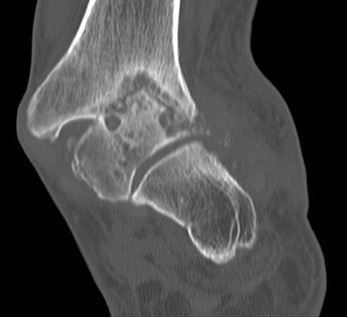

- CT – esp in trauma (Figure 7a), but also navicular stress fractures (Figure 7b)

Figure 7a: CT scan demonstrates multi-fragmentary fracturing of the navicular